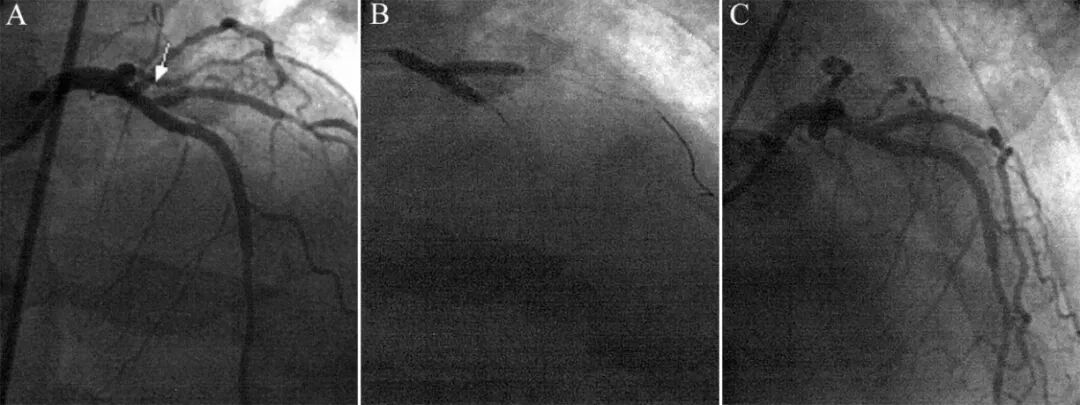

图10 支架回拉法处理对角支开口病变[10]。

对角支开口狭窄80%,前降支狭窄20%(A)。前降支4.0×20mm球囊4atm低压扩张,同时对角支3.0×13mm支架回拉,遭遇阻力并出现压迹时,16atm释放支架(B),最后结果良好。